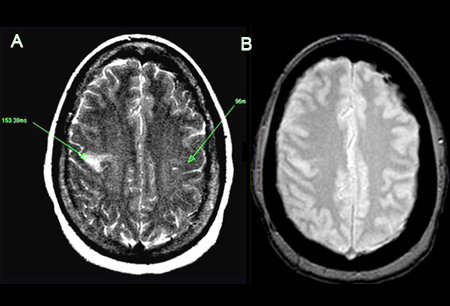

Acidente vascular cerebral (AVC) isquêmico

(A) Uma imagem de ressonância nuclear magnética (RNM) ponderada em T2 mostrando hiperintensidade, representando T2 prolongado. Exibição de T2 anormal de 153.38 ms à esquerda, comparado com o lado contralateral normal (96 ms). Observe que a lesão é localizada no giro frontal ascendente. (B) Imagens de ecogradiente detectam compostos de hemossiderina devido à susceptibilidade magnética do ferro. Neste caso, o resultado é negativo

Do acervo pessoal do Dr. Eric E. Smith; usado com permissão